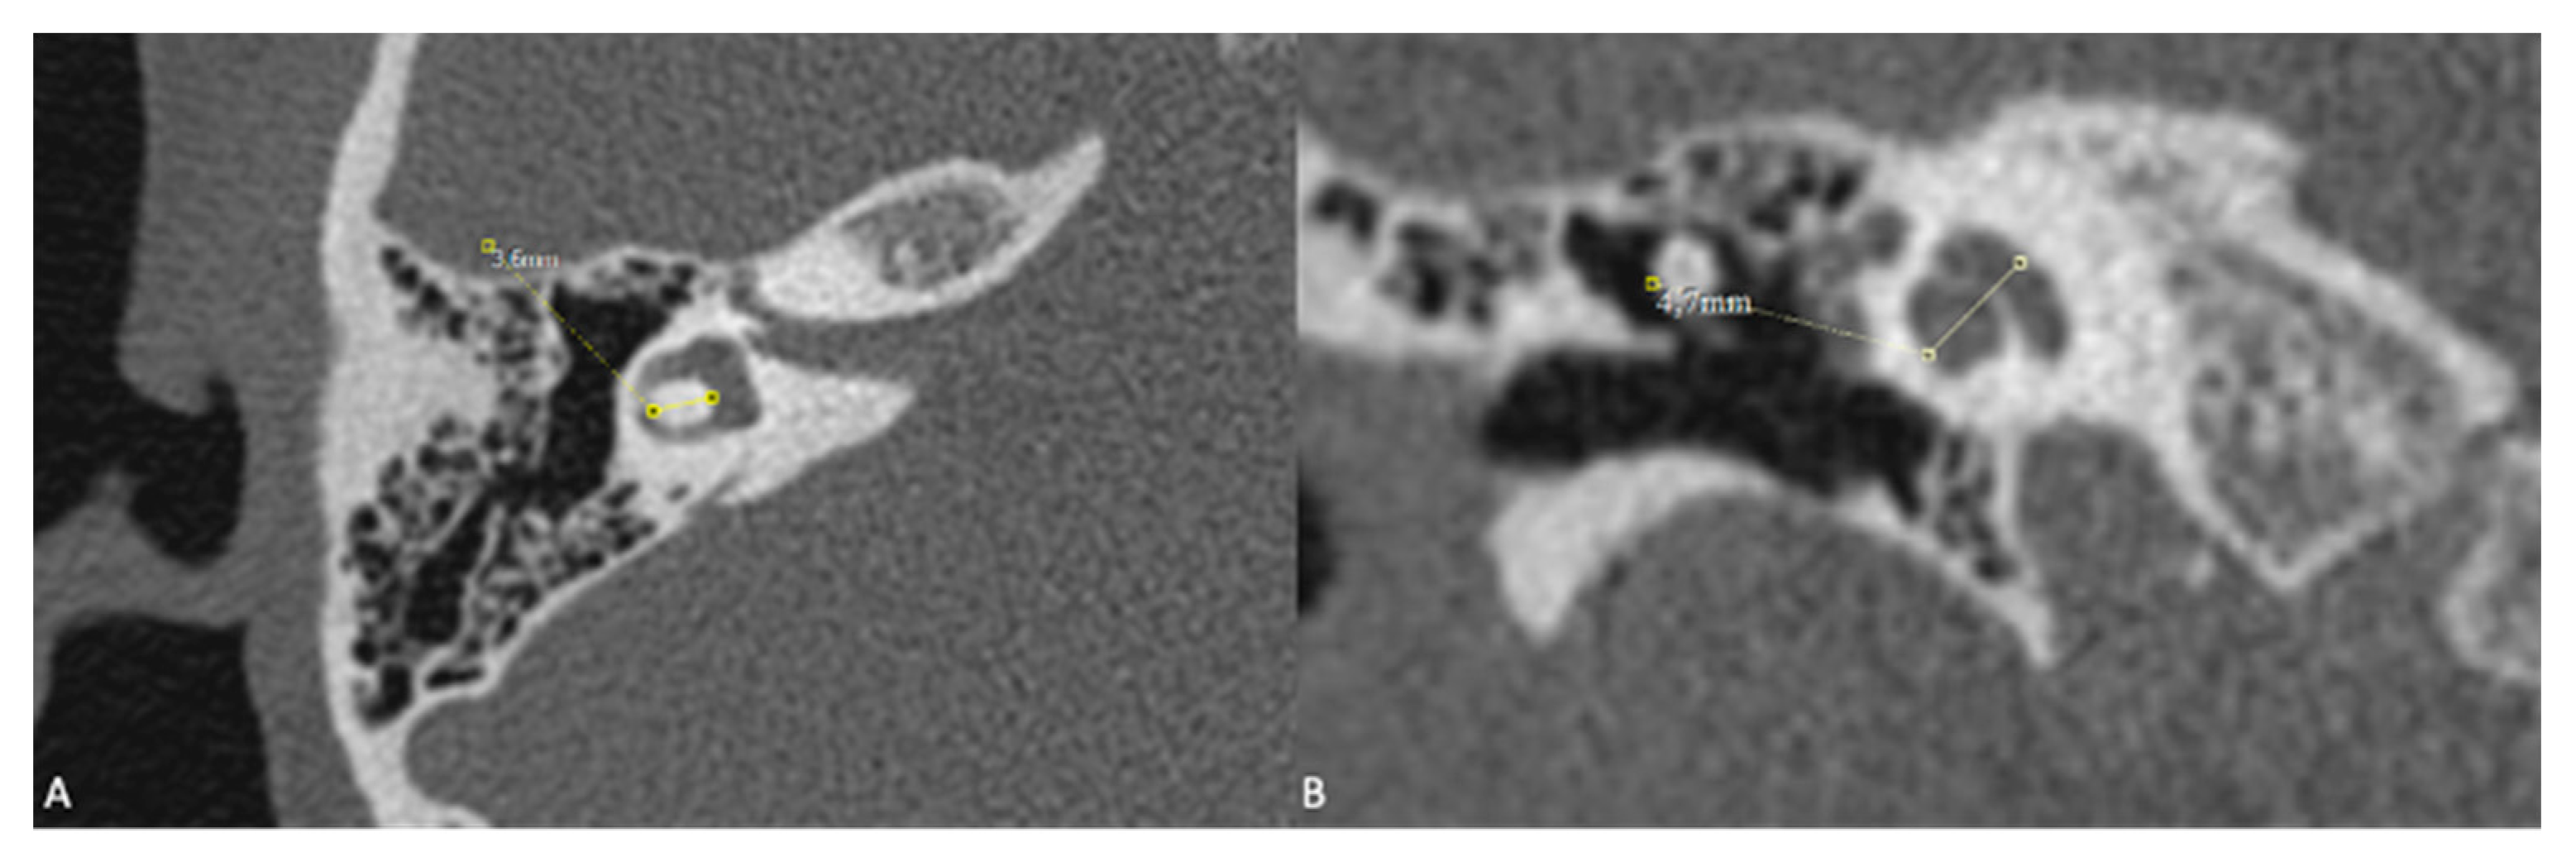

For the inner ear structures, we assessed the density of the otic capsule, the spiral structure, and the internal relationships, including the densities of the cochlea, vestibule, and semicircular canals. Cochlear malformations were classified according to the classification initially proposed by Jackler et al. [5] and later refined by Sennaroğlu and Saatçi [6]. Additionally, measurements of the cochlear height in the coronal section and the diameter of the bony island of the lateral semicircular canal (LSCC) in the axial section, as described by Purcell et al. [13], were taken for all patients to explore differences between congenital and acquired cases (Figure 2). Axial sections were aligned parallel to the LSCC, and coronal sections were defined as perpendicular to the axial sections. The VA was examined, and cases where the diameter exceeded 1.5 mm at its midpoint were identified as having a large VA.

Figure 2. A) Measurement of LSCC (left semicircular canal) bony island in the axial section and B) measurement of the height of the cochlea in the coronal reformatted section as described by Purcell et al.